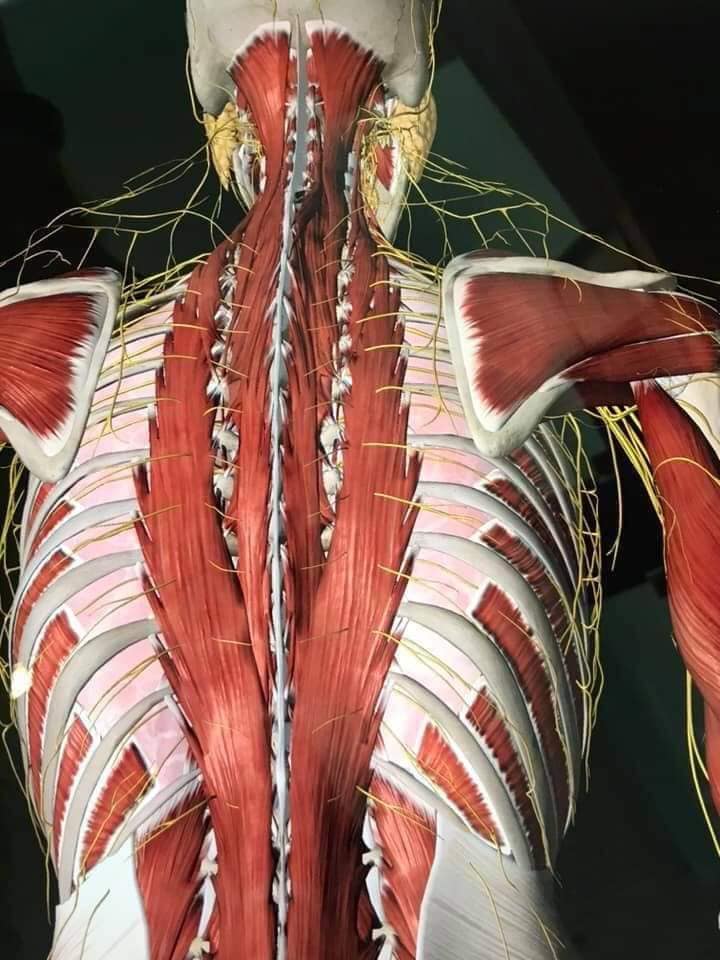

Спинні м'язи

Спинні м'язи виконують функції підтримки хребта, а також дозволяють здійснювати рухи тулуба.

Поверхневі спинні м'язи

М'язи, що піднімають лопатку: Трапецієподібний м'яз: великий м'яз, що покриває верхню частину спини. Його функція - підтримка і рух лопаток, а також забезпечення стабільності хребта.

М'язи, що ведуть лопатку до хребта: Широкий м'яз спини: великий м'яз, що розташований в нижній частині спини. Він відповідає за рухи плечей і лопаток, а також за розширення верхньої частини тулуба.

Глибинні спинні м'язи

М'язи, що забезпечують стабільність хребта: М'язи, що розташовані між хребцями: включають мускулатуру, яка забезпечує стабільність і підтримку хребта, а також дозволяє здійснювати рухи хребта.

М'язи, що здійснюють ротацію та нахили

М'язи, що забезпечують ротацію хребта: Ротаційні м'язи: допомагають у здійсненні обертальних рухів тулуба, а також у підтримці рівноваги і стабільності хребта.